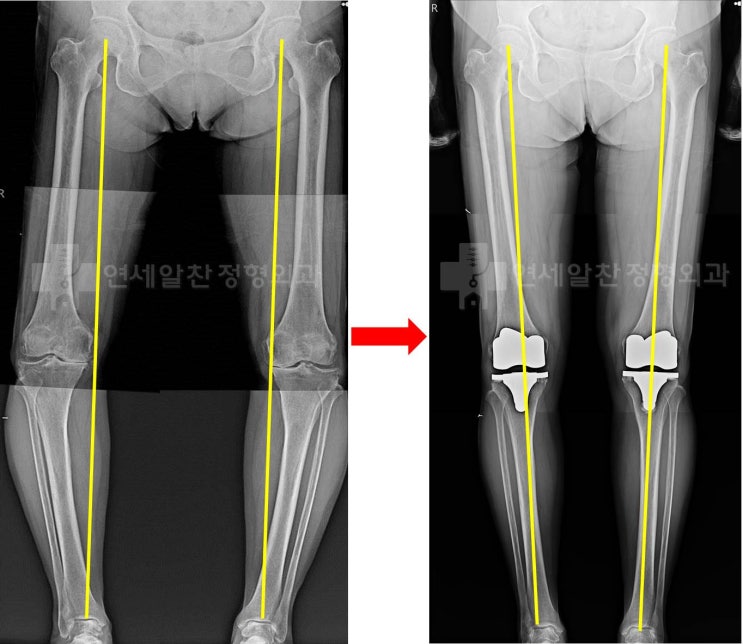

무릎 퇴행성 관절염에서 인공관절 전치환술 및 결과에 대한 고찰

71세 여자 환자로 10년 이상의 무릎 통증을 주소로 내원하였다. 환자는 약물 및 연골주사, 통증주사 를 반...